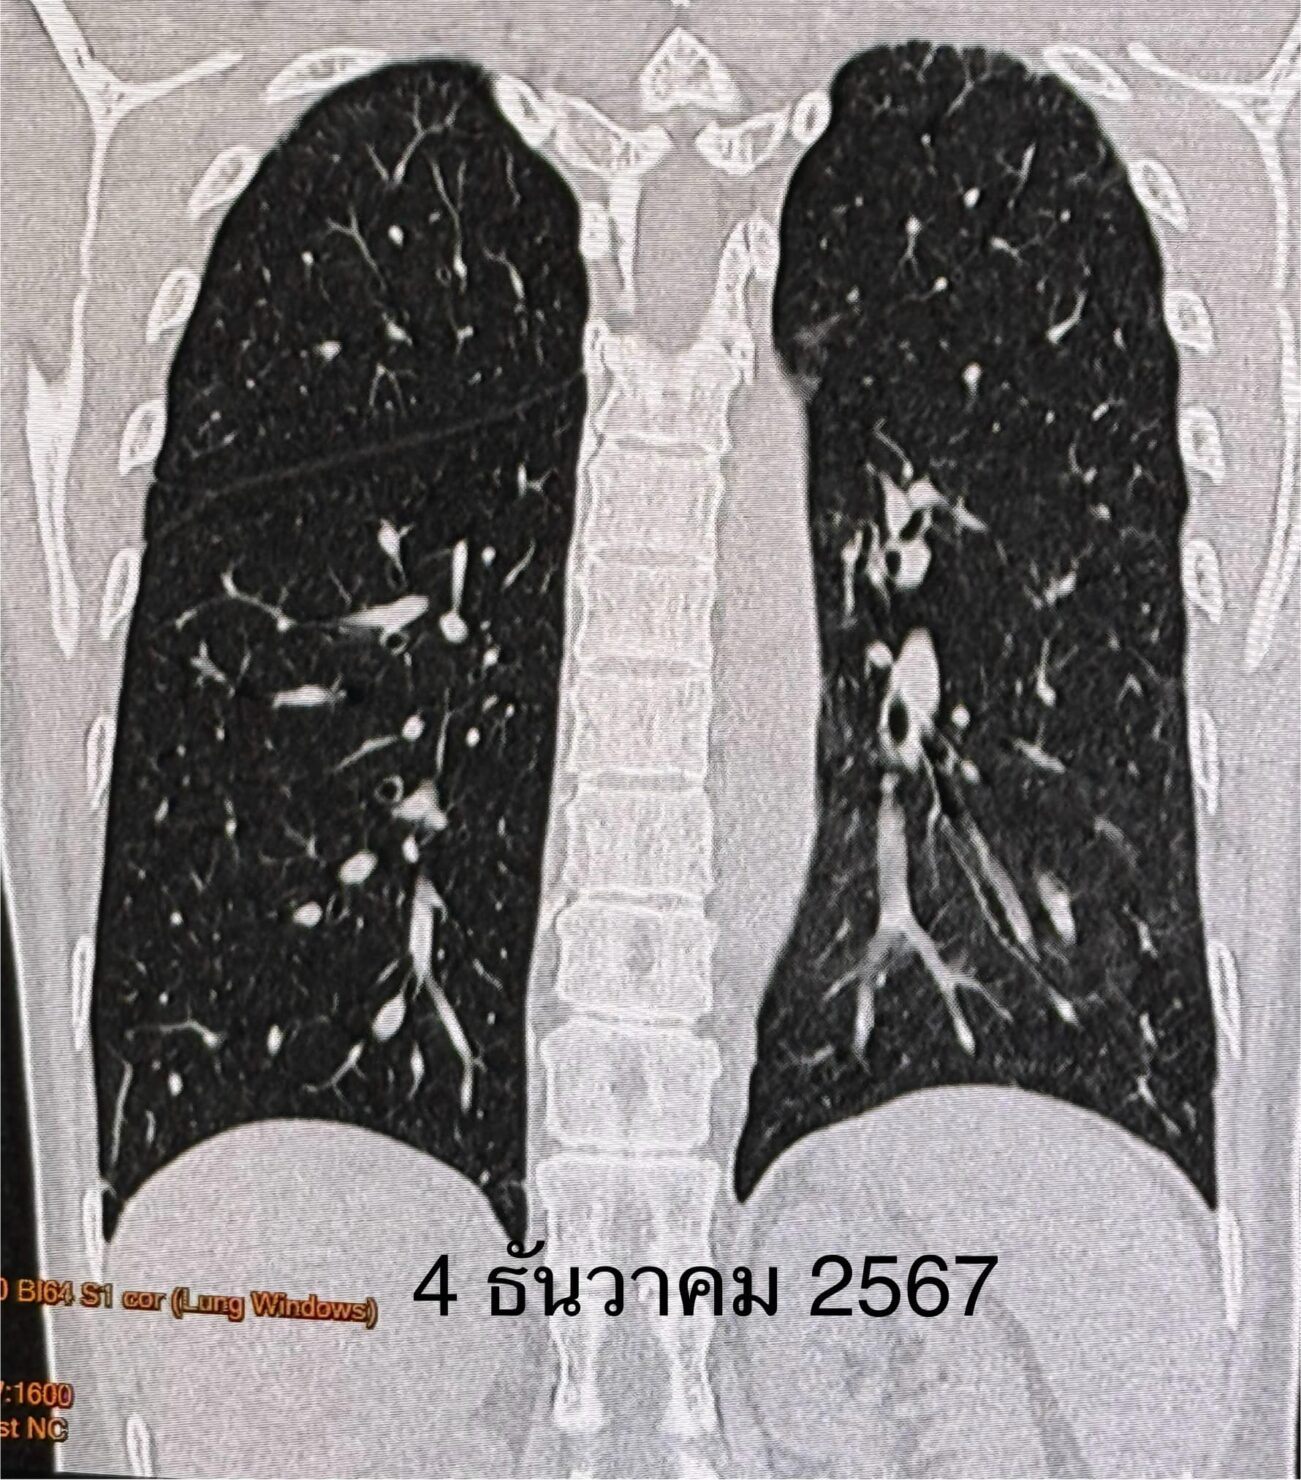

เอกซเรย์ปอดมีฝ้าขาวที่ปอดซ้ายด้านล่าง(ดูรูป ) คอมพิวเตอร์ปอดเห็นฝ้าขาวที่ปอดซ้ายด้านล่าง(ดูรูป) ทำสมรรถภาพปอดพบความจุของปอดลดลง เจาะเลือดค่าอักเสบของเลือดสูงเล็กน้อย ESR 31, hs-CRP 11.2, ANA positive 1:1280 Anti-MDA5 positive 3+, ค่าอักเสบของกล้ามเนื้อ CPK ปกติ 62

ผู้ป่วยได้วัคซีนไฟเซอร์เข็มที่ 3 เดือน ม.ค. 2566 เพราะกลัวว่าหากติดไวรัสโควิด-19 อาจป่วยรุนแรง เนื่องจากกำลังกินยากดภูมิคุ้มกัน ปรากฏว่า 5 วันหลังฉีดวัคซีนไฟเซอร์ ผื่นที่หน้า ข้อมือ ข้อศอก คอ หลังส่วนบน กลับมาเป็นมากขึ้น ไอ เหนื่อยเวลาออกกำลังกาย เอกซเรย์ปอดและคอมพิวเตอร์ปอดเห็นฝ้าขาวเพิ่มขึ้นที่ปอดด้านล่างทั้ง 2 ข้าง(ดูรูป)

ผู้ป่วยติดเชื้อไวรัสโควิดครั้งแรกวันที่ 5 ธค. 2566 มีอาการน้อยมาก ได้ยาโมลนูพิราเวียร์ หายเร็วทั้งๆที่กินยากดภูมิคุ้มกัน ไม่มีอาการหลังการติดเชื้อไวรัสโควิด ค่อยๆ ปรับลดยากดภูมิคุ้มกันลงเรื่อยๆ ผิวหนังกลับมาเป็นปกติ เอกซเรย์ปอด และคอมพิวเตอร์ปอดดีขึ้นเกือบปกติ(ดูรูป) ทำสมรรถภาพปอดความจุของปอดกลับมาปกติ วันที่ 17 ธ.ค. 2567 หลังจากรักษา 2 ปีกว่า ได้หยุดยากดภูมิคุ้มกันทุกตัวเหลือแต่ไฮดรอกซีคลอโรควิน กิน 1 เม็ดวันเว้นวัน ค่าอักเสบของเลือดปกติ ESR 8, hs-CRP 0.4